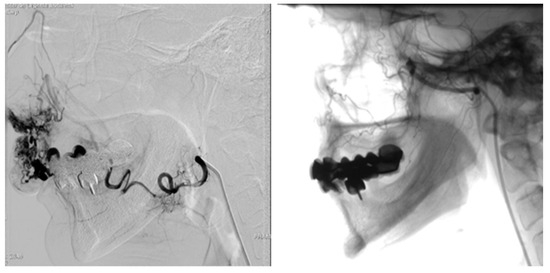

3.3.3. Therapy